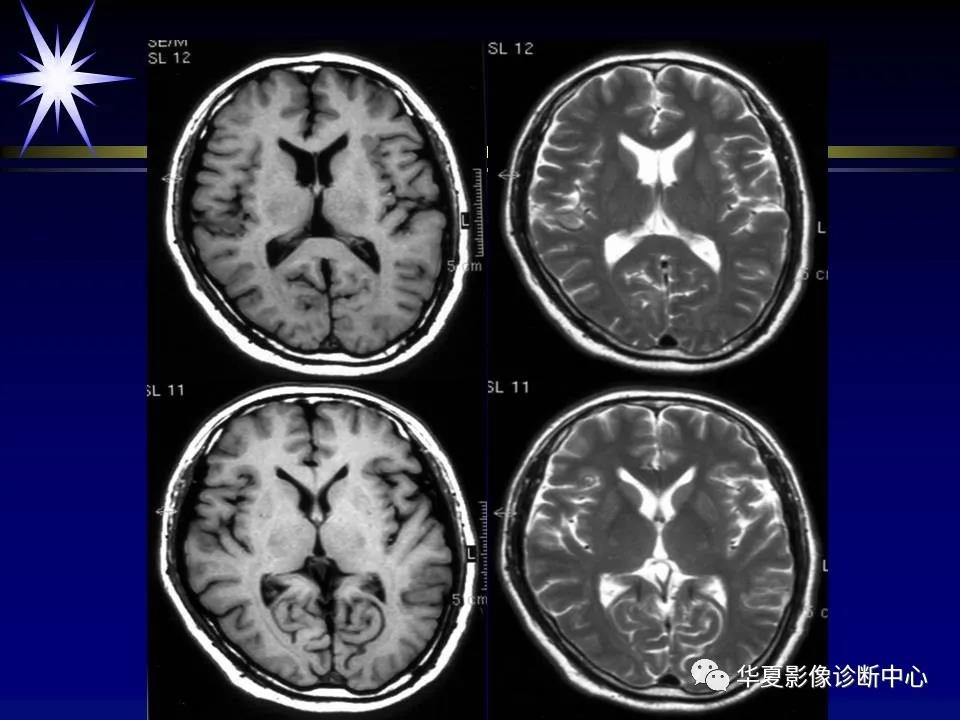

来源:华夏影像诊断中心